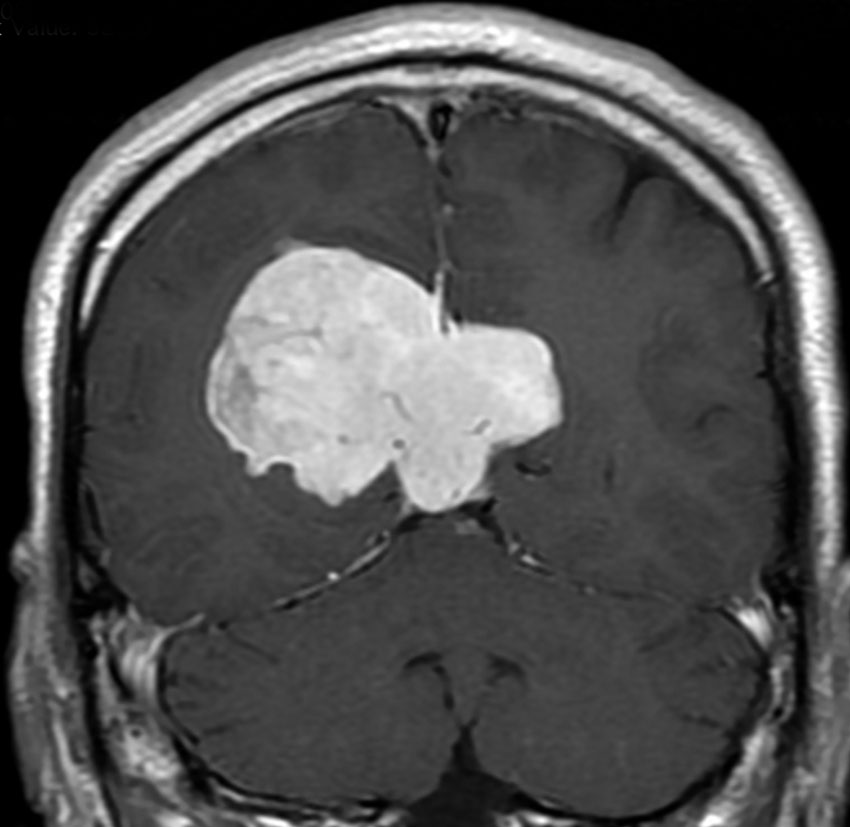

典型的な髄膜腫

この髄膜腫は中程度の大きさのものです。円蓋部髄膜種という最も多い最も手術の簡単なタイプです。麻痺や失語症やてんかんなどの症状はありません。とても美しくて若い女性の髄膜腫でしたが,子供に遺伝はしませんし,癌などと違ってタバコなどこれといった原因がなくて発生するものです。

MRIでの髄膜腫の見え方は撮影の仕方によっていろいろです。左からT1強調画像,T2強調画像,フレア画像といいます。腫瘍の横に小さく白い領域がありますが,これは脳の腫れた部分で脳浮腫といいます。髄膜腫があると周囲に脳浮腫が生じることがあります。

最も見やすいのが,ガドリニウム造影剤を注射して撮影するものです。一般的に髄膜腫は造影剤で白く映し出されます。この腫瘍は左脳側にあります。MRIの軸面という輪切りの写真では左右が逆になりますから注意してください。脳を下から見た図になっています。MRIはいろいろな方向から腫瘍を見ることができますが,右は冠状断という正面から見た図です。よく見ると腫瘍の上と下のはじっこに線状に糸を引いたように造影される部分があります。これをテールサイン(しっぽのサイン)といいます。腫瘍が硬膜に沿って延びている可能性があることを示しています。